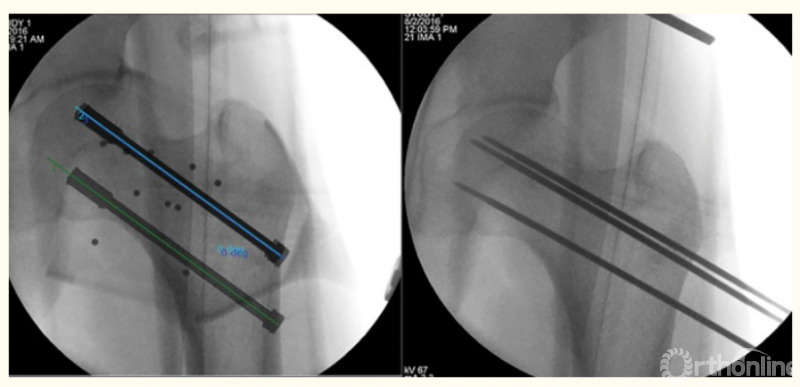

2、骨盆髋臼骨折的机器人辅助手术

3、股骨颈骨折的机器人辅助手术